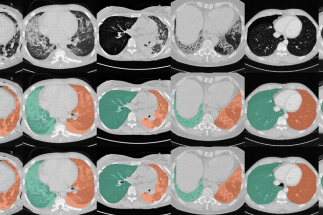

Segmentation Automated segmentation of anatomical structures is a crucial step in many medical image analysis tasks. We show that a basic approach - U-net - performs either better, or competitively with other approaches on both routine data and published data sets, and outperforms published approaches once trained on a diverse data set covering multiple diseases. Training data composition consistently has a bigger impact than algorithm choice on accuracy across test data sets. (Hofmanninger et al, 2020)